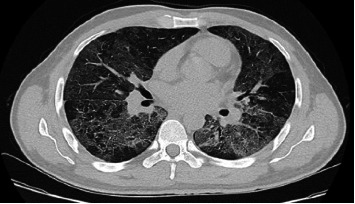

Introduction: People living with HIV (PLWH) are highly susceptible to respiratory infections, particularly pneumonia, which is often polymicrobial. A rapid decline in CD4 T lymphocytes, especially with concurrent influenza, increases the risk of Pneumocystis jirovecii pneumonia (PCP). Case Presentation: This report discusses a newly diagnosed Acquired Immunodeficiency Syndrome (AIDS) patient with influenza and PCP coinfection, highlighting diagnosis, follow-up, and prognosis. Conclusions: Community-acquired pneumonia is common in PLWH, especially among those not receiving antiretroviral therapies (ART). Co-infections with bacterial, viral, and fungal pathogens are common. Early identification of etiological agents and prompt treatment are crucial for improving patient outcomes.

Abstract Image